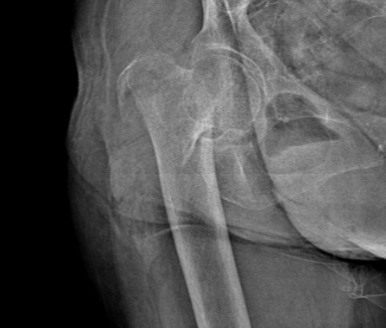

这次李奶奶在家中不慎摔倒,伤至右大腿,因语言功能障碍,未能及时被家人发现。次日在被家人发现其右大腿肿胀后, 2023年8月14日再次送至谢桥医院骨科进行治疗。经检查,诊断为“右股骨干骨折”。

入院后,谢桥医院骨科团队一边为李奶奶完善相关检查等治疗,一边进行多学科会诊紧急讨论。考虑到李奶奶是高龄骨折,同时在此之前已经进行过一次关节置换,针对这些手术难点,以及术中可能出现的突发情况,术前谢桥医院骨科团队经过反复讨论,并与其家属沟通后,最终确定了严密的手术计划和全面的治疗方案,决定为李奶奶施行“右侧股骨干骨折切开复位内固定术”。目的便是为了提高术后康复效果,极大程度减少并发症。